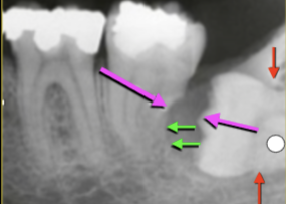

What is the Green Dot?

Submandibular Fossa

What is the Purple Dot?

Radicular Cyst

What is the dental anomaly?